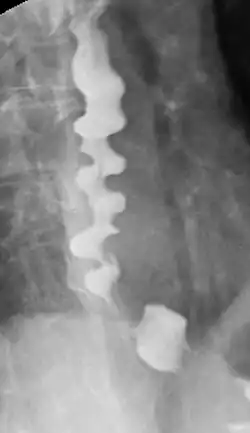

Corkscrew appearance of the esophagus.

Several radiographic findings are suggestive of DES, such as a "corkscrew esophagus" or "rosary bead esophagus" appearance on barium swallow x-ray, although these findings are not unique to DES.[2]